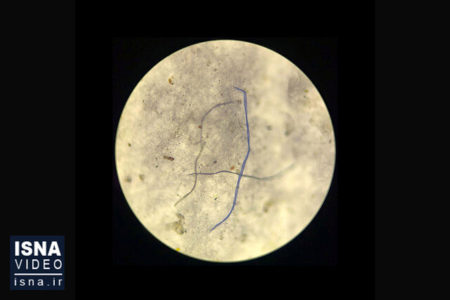

ویدئو / ردپای میکروپلاستیک‌ها در گوشت و خون و شیر

نتایج مطالعات دانشمندان هلندی درباره گسترش زباله‌های پلاستیکی نشان می‌دهد که گوشت‌، خون و شیر دام‌ها به میزان قابل توجهی دچار آلودگی پلاستیکی شده‌اند، به طور دقیق‌تر، تمام نمونه‌های بررسی‌شده از خوراک دام‌ها و همچنین نمونه‌ خون‌های گرفته‌شده از ‌آن‌ها، دارای میکروپلاستیک بوده‌اند. همچنین، نمونه شیرهای بررسی‌شده در ۷۲ درصد موارد حاوی پلاستیک هستند و این میزان، برای محصولات گوشتی، ۷۵ درصد است.